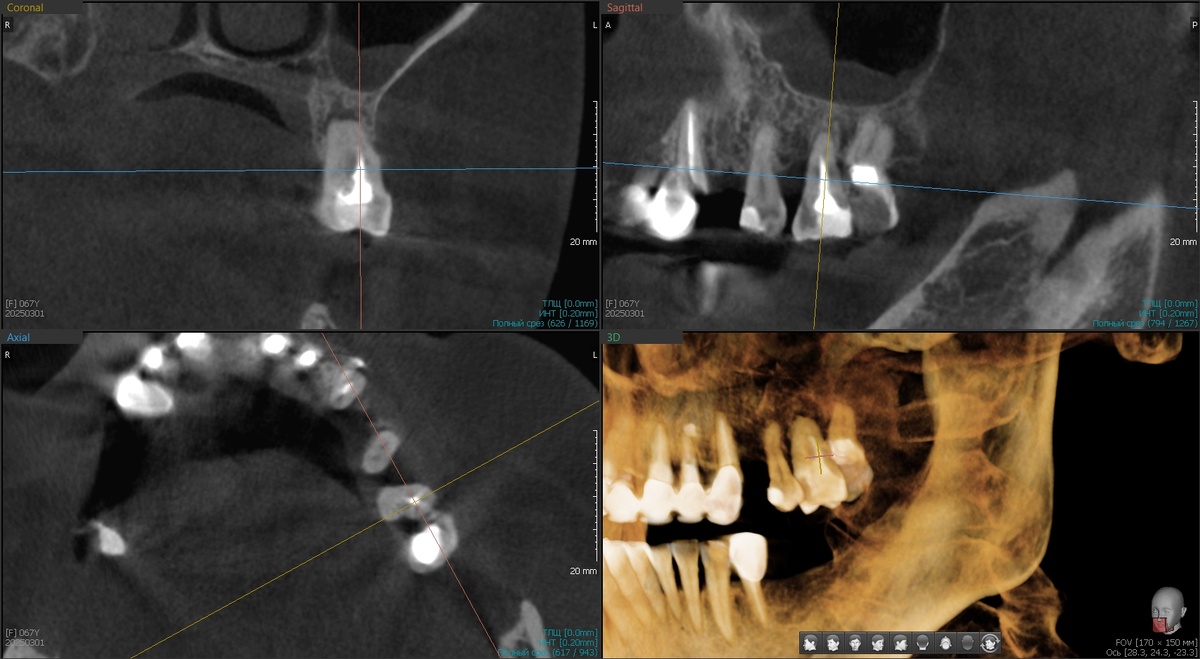

План такой - установить 4 классических имплантата + 2 птеригоидных (крыловидных) в дистальных отделах верхней челюсти. Птеригоидные - это такие длинные имплантаты (20-25 мм), которые проходят через всю челюсть и фиксируются в крыловидном отростке клиновидной кости. Надёжный способ избежать синус-лифтинга при атрофии для данного клинического случая.

Удалили остатки зубов на верхней челюсти, установили птеригоидные имплантаты, которыетребуют ювелирной точности. Сверлим под углом 45 градусов, проходим через толщу кости, целимся в крыловидный отросток. Промах на миллиметр - и можем попасть в крыловидное венозное сплетение или повредить нерв.

Но шаблон, спланированный в цифре, не даёт промахнуться. Два птеригоидных встали идеально.

Затем, по шаблону, установили 4 остальных имплантата - классика: